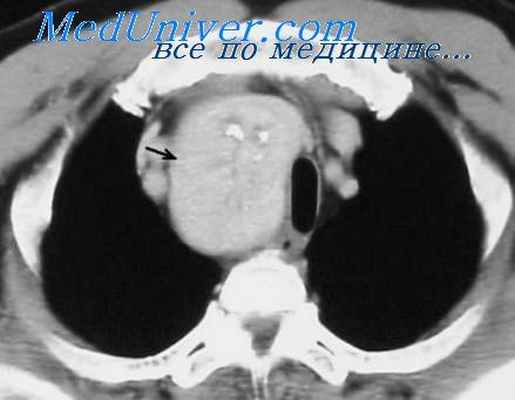

На компьютерной томограмме верхнего средостения на уровне III грудного позвонка определяется тень увеличенной щитовидной железы размерами: правая доля — 6,0 х 4,5 см,

Рис. 1. Рентгенограмма верхнего средостения в прямой проекции.

Загрудинный кольцевидный зоб. Контуры трахеи нечеткие.

Рис. 2. Компьютерная томограмма на уровне III грудного позвонка.

Щитовидная железа в виде кольца охватывает трахею и суживает ее. В обеих долях щитовидной железы кальцификаты и небольшие кистозные полости.

левая доля — 6,0 х 5,0 см. Контуры щитовидной железы неровные, бугристые, структура неоднородная с наличием каль- цификатов и небольших кистозных полостей (рис. 2). Денси- тометрические показатели железы снижены от +56 до + 84 ед. Ни. Щитовидная железа в виде кольца охватывает трахею, диаметр ее просвета сужен больше, чем наполовину. При реконструкции томографических срезов длина правой доли 11,0 см, левой— 10,5 см. Таким образом, нижний полюс щитовидной железы заходил за край яремной вырезки на 7 см (загрудинный зоб). На операции эти данные подтвердились полностью (рис. 3).